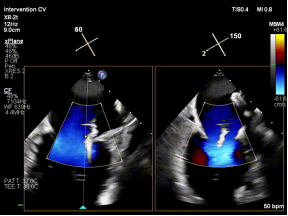

【图片1:术前超声图】

病例1为典型退行性二尖瓣脱垂(DMR),术前超声提示外交界瓣叶明显脱垂,反流程度达重度(4+),伴随活动后气促等心衰症状。由于病变位于“红区”,瓣叶结构复杂、对合不稳定,属于TEER治疗中的高难度类型。

手术中,团队在经食管超声心动图(TEE)引导下精准完成房间隔穿刺,为器械操作提供良好空间;建立稳定输送路径,使导向系统与二尖瓣平面充分对齐;利用X-plane及三维超声反复定位脱垂区域,微调器械角度,实现对目标瓣叶的精准抓取;确认夹持质量后释放装置,最终完成修复。